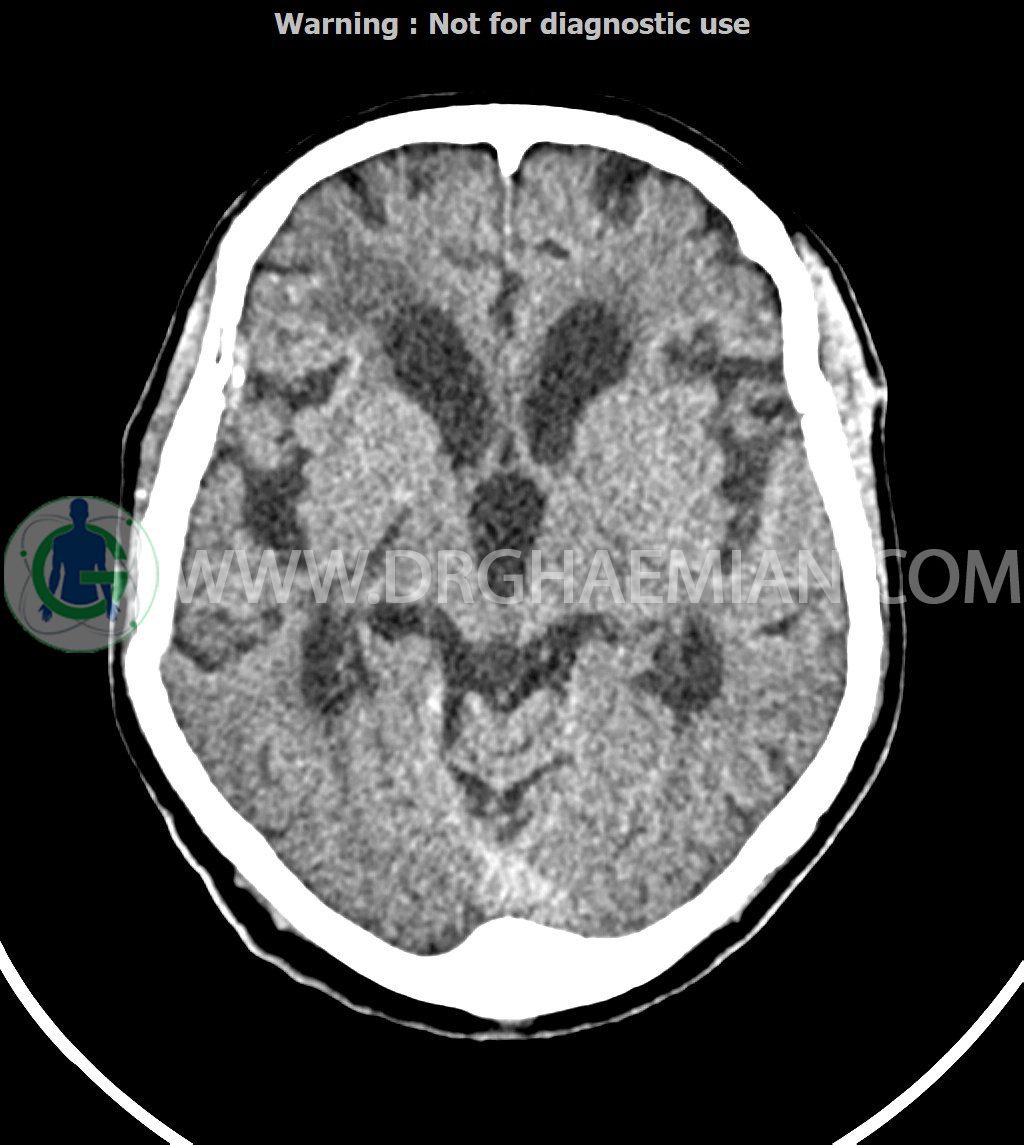

سی تی اسکن مغز با استفاده از اشعات ایکس تصاویری از سر که شامل جمجعه، مغز، حفره های چشمی و سینوس ها است ایجاد می کند. در این کیس پنوموسفالوس مختصر در فرونتوپاریتال راست مشاهده شده.

سی تی اسکن اسپیرال از مغز بدون کنتراست وریدی ( مولتی دیدکتور 16 با مقاطع ظریف و بازسازی های ساژیتال و کرونال):

-شواهد جراحی مغز شامل کرانیوتومی فرونتوپریتوتمپورال سمت راست ، هماتوم و آمفیزم زیرجلدی و پنوموسفالوس مختصر در فرونتوپاریتال راست

-هماتوم ساب دورال (SDH ) مختصر (حداکثر ضخامت 4mm ) در فرونتوپاریتال راست و همچنین در تنتوریوم و فالکس خلفی

-آتروفی خفیف و منتشر پارانشیم مغز (1 GCA )

-ونتریکولومگالی در بطن های جانبی بصورت نامتناسب با اتروفی کورتیکال که می تواند در زمینه NPH (normal pressure hydrocephalus) باشد. تطابق با یافته های بالینی توصیه می شود.

-هایپودنسیتی منتشر در نواحی پری ونتریکولار به نفع Small vessel disease

-کلسیفیکاسیون فالکس قدامی و غده پینه آل (یافته نرمال با توجه به سن ) مشهود است.